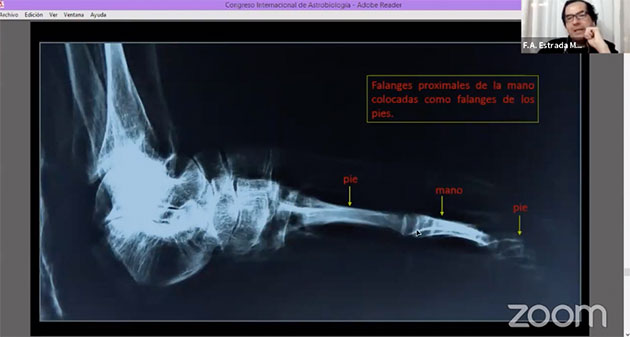

Hierzu wurden an den Händen jeweils ein Finger und die Daumen entfernt und mit diesen die auf die gleiche Weise bearbeiteten Füße, bzw. deren verbliebene Zehen verlängert, um den Füßen ein zusätzlich exotisches (vermeintlich außerirdisches) Aussehen zu verleihen. Zu erkennen ist dies u.a. daran, dass die Spalten zwischen den Knochen normalerweise viel geringer sein sollten (Abb. 61). Der Umstand, dass dieser Abstand zu groß ist zeigt, dass hier Knochen regelrecht zusammengebaut wurden. Die Spuren dieser Bearbeitung sind erneut auf den Röntgenaufnahmen zu erkennen. Anhand eines Vergleich von Röntgenaufnahmen normaler (vollständiger) Hände (Abb. 62, 63 r. u. m) mit Marias Füßen (Abb. 63, 63 l.) verdeutlichen die Schaubilder (Abb. 62, 63), welche Knochen wo entfernt und hinzugefügt wurden.